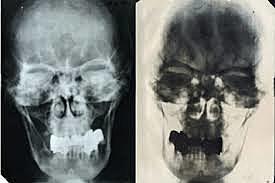

Identificación del cuerpo de adolfo hiitler que fue reconocido por el doctor Sognnaes debido al póntico del incisivo superior que realizo el mismo y a su perdida del hueso alveolar y sus endodoncias.